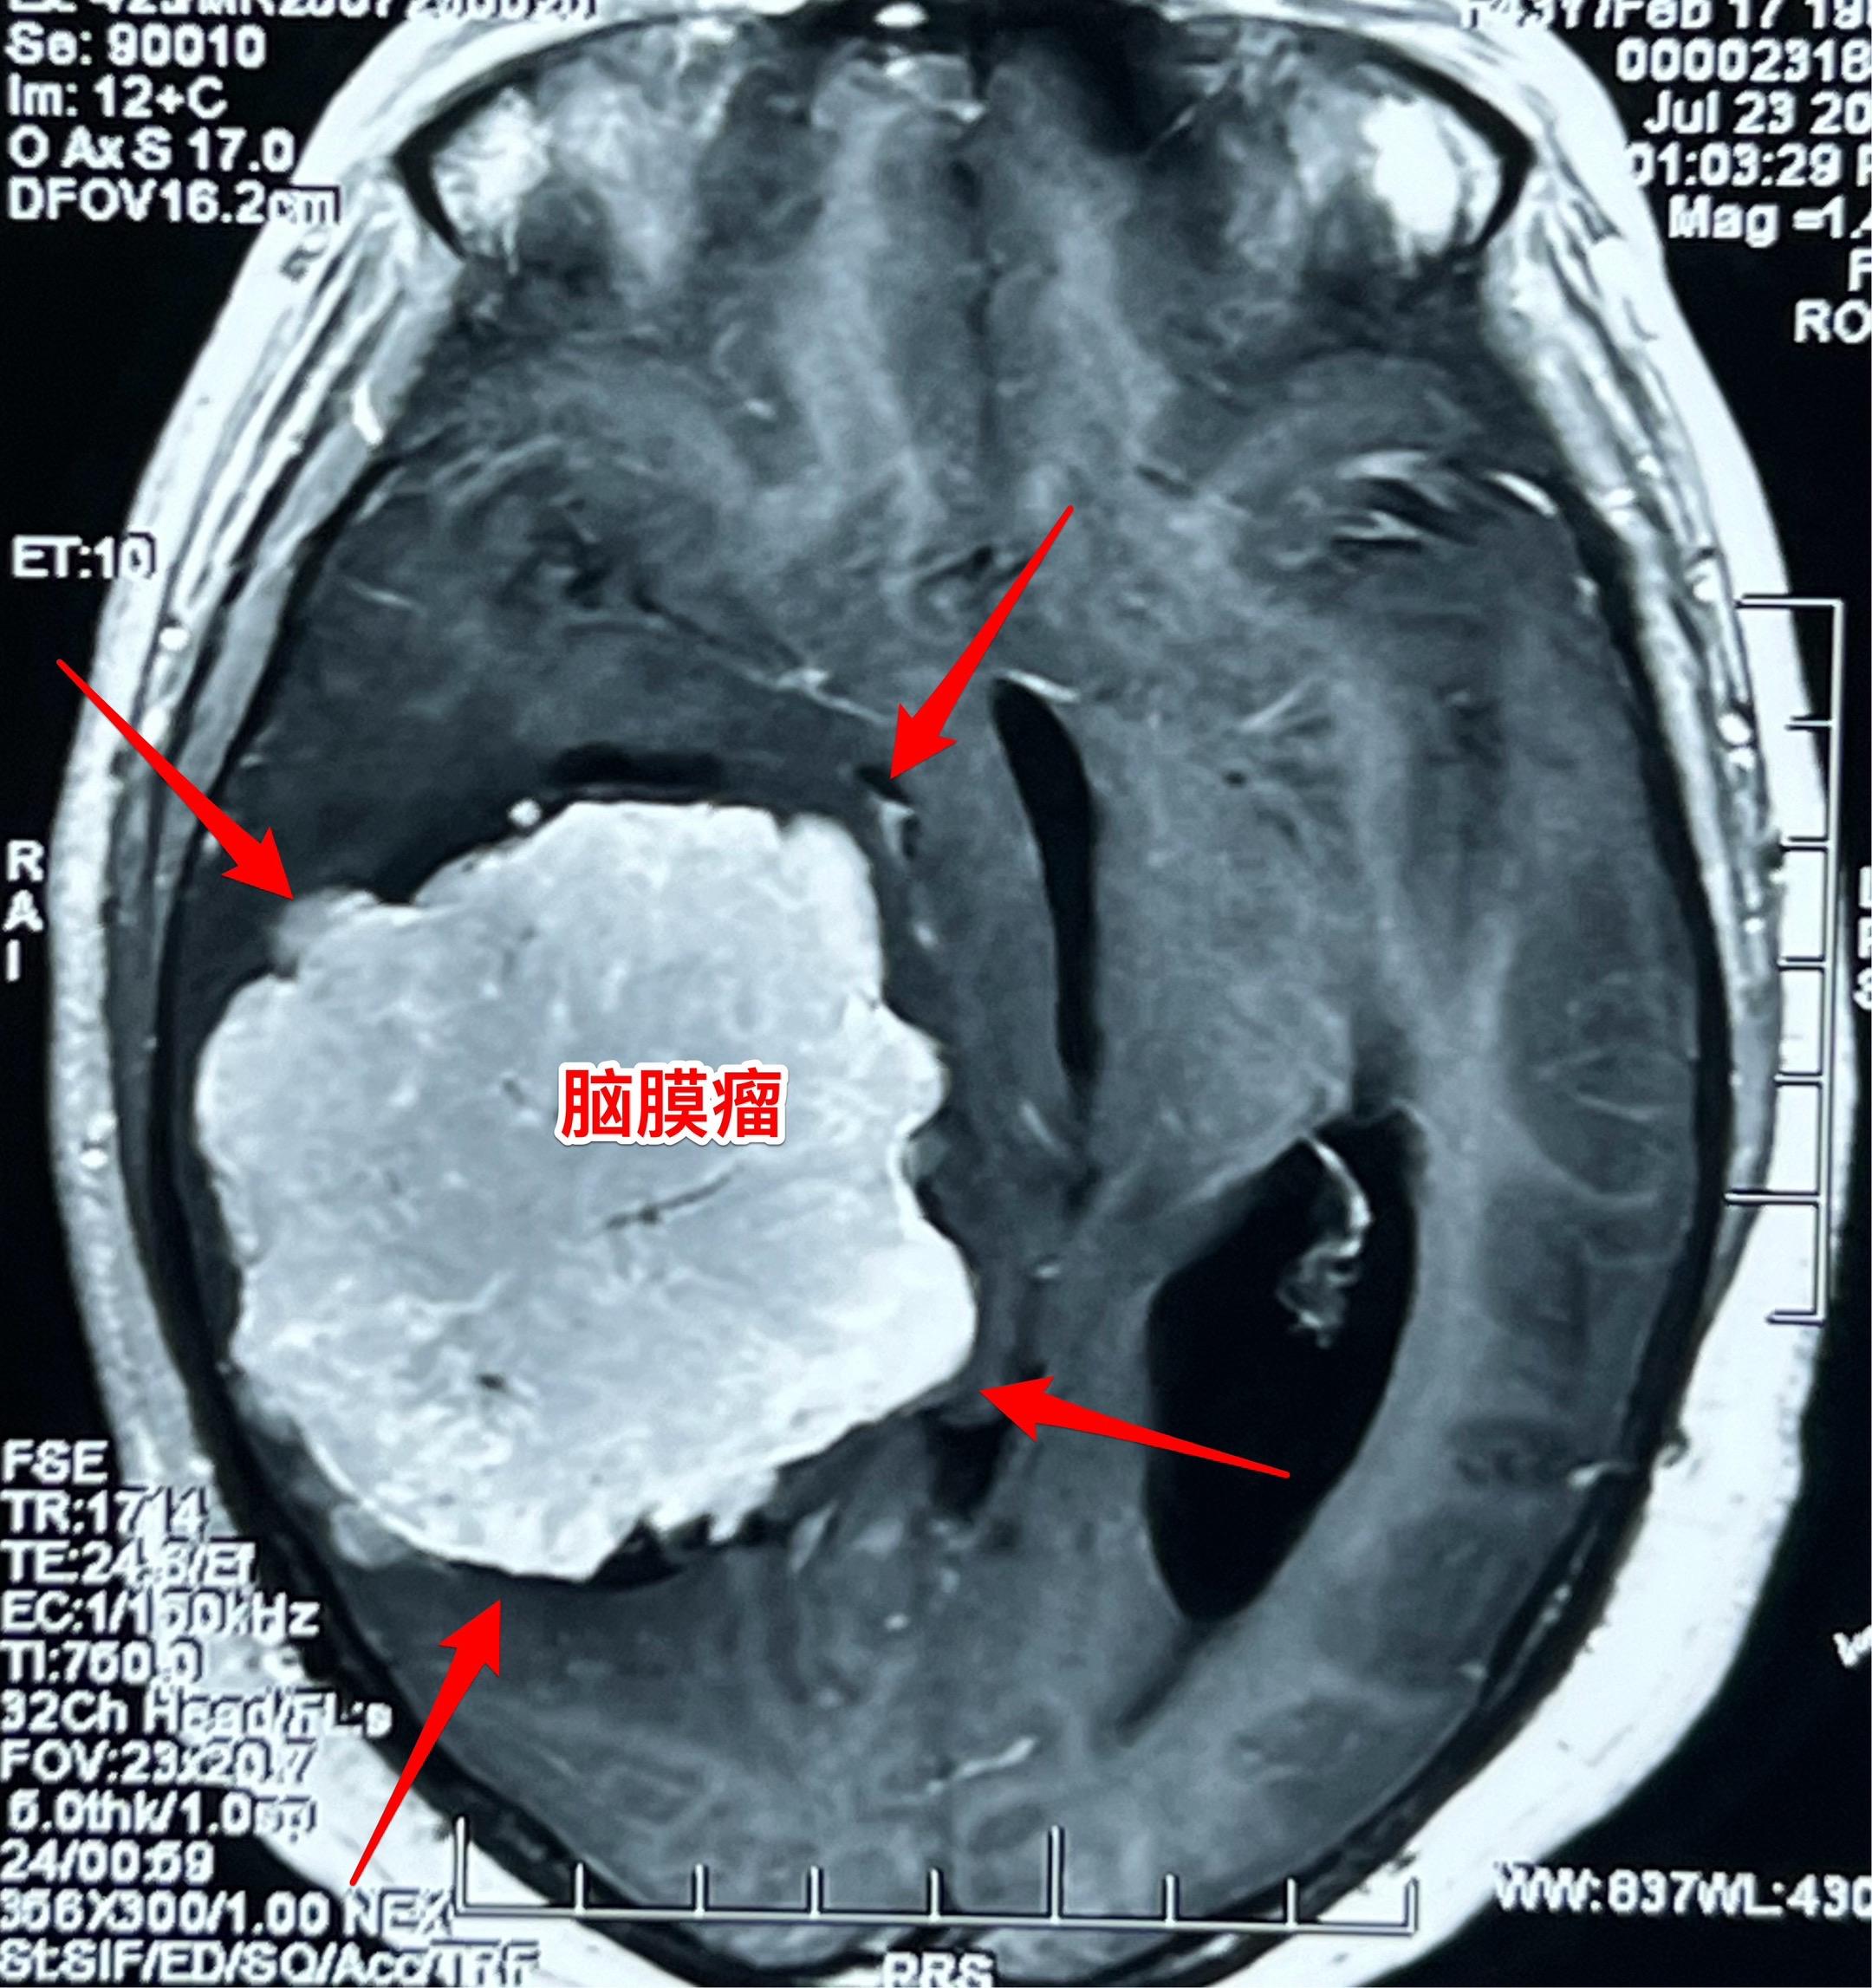

藏族牧民脑肿瘤被发现时像鸡蛋一样大。青海省黄南州藏族牧民,43岁,女性,平时以放养牦牛为生,家里有一百多头牦牛,她夫妻二人完全不能说汉语。 她头痛五年了,视力下降一年,迟迟没有就医,今年七月份因视力很差了才到西医医院检查,发现病根儿是脑膜瘤。如图所示,脑膜瘤像鸡蛋一样大。 发现脑肿瘤后,他们第一步是找活佛预判凶吉,指导治疗方向! 2025年8月1日作了手术,将肿瘤完全切除。希望她能顺利出院!